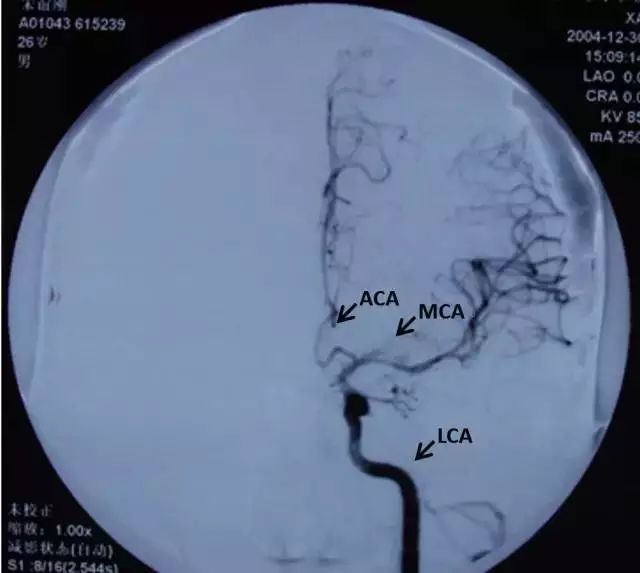

以下是颈内动脉、ACA和大脑中动脉的正、侧血管造影。